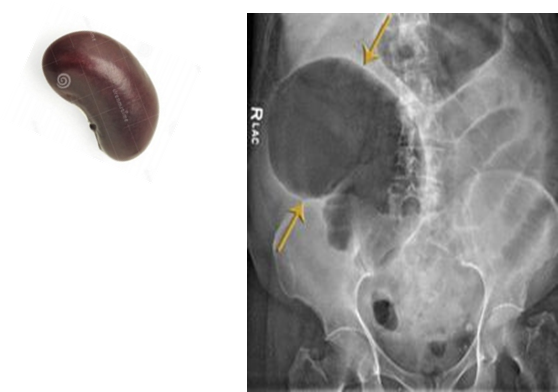

Caecal volvulus

Radiological Appearance:

Kidney bean sign